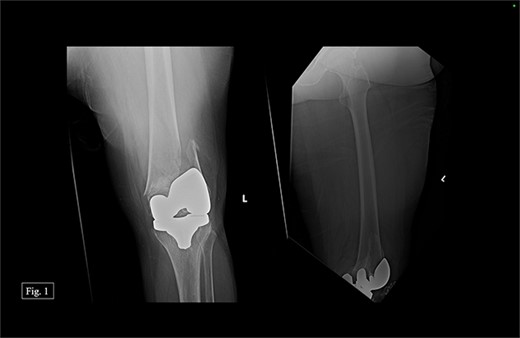

In February 2020, the patient presented with a left distal periprosthetic femur fracture (Su Type II) after attempting to walk to the bathroom and falling onto her left knee (Fig. 1). Due to minimal bone availability for distal fixation around the prosthesis, the patient was indicated for a DFR, allowing immediate weight bearing.